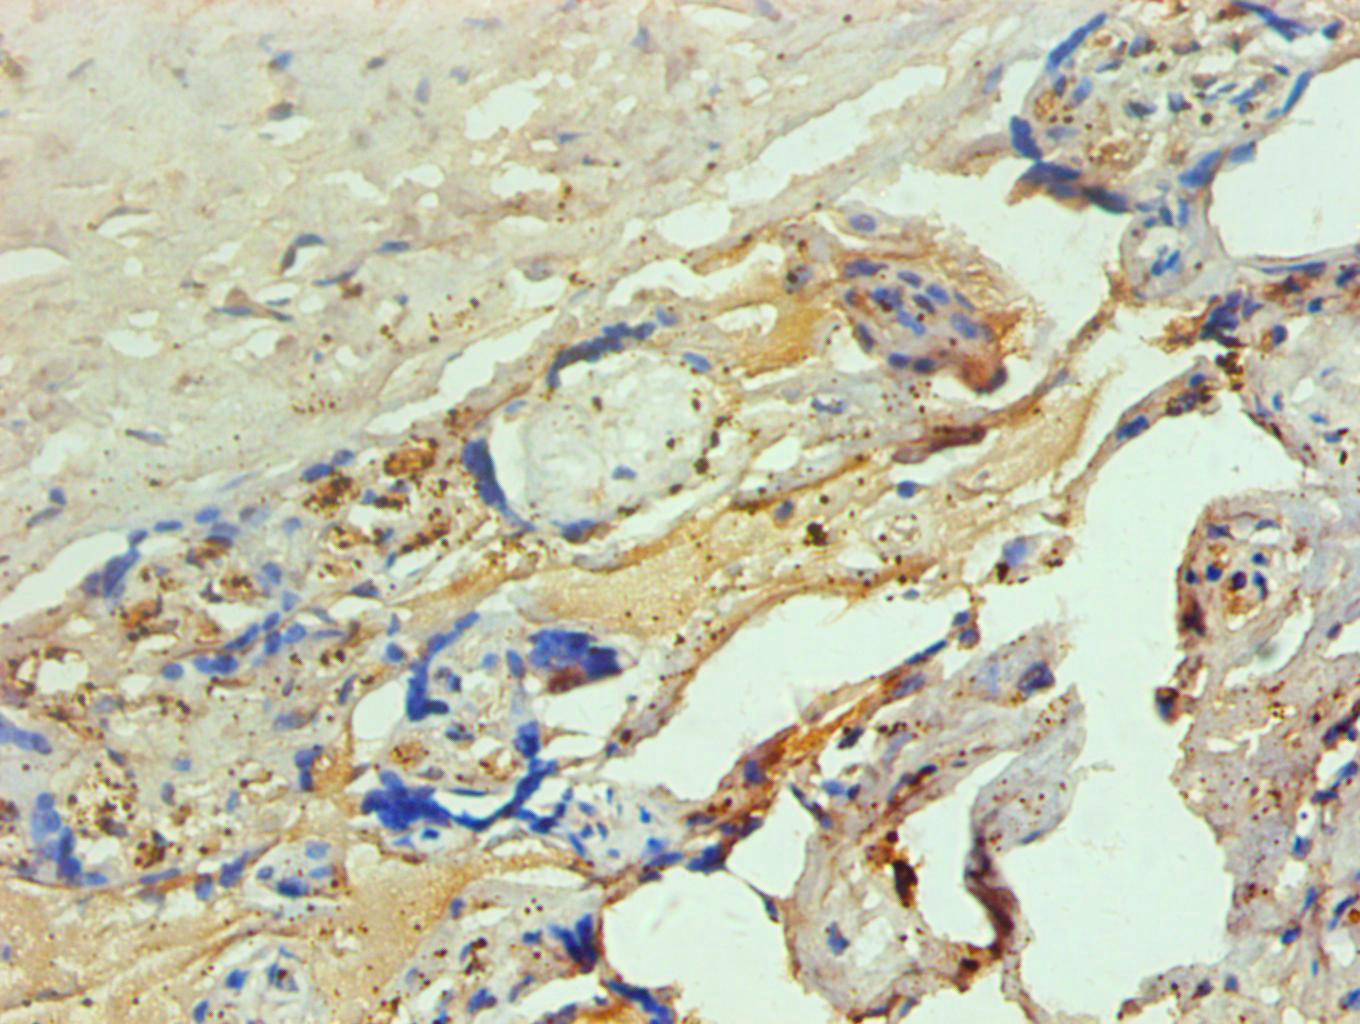

图片:

Immunohistochemical analysis of paraffin-embedded human spleen tissue using #42015 at dilution of 1:200.

Immunohistochemical analysis of paraffin-embedded human placenta tissue using #42015 at dilution of 1:200.